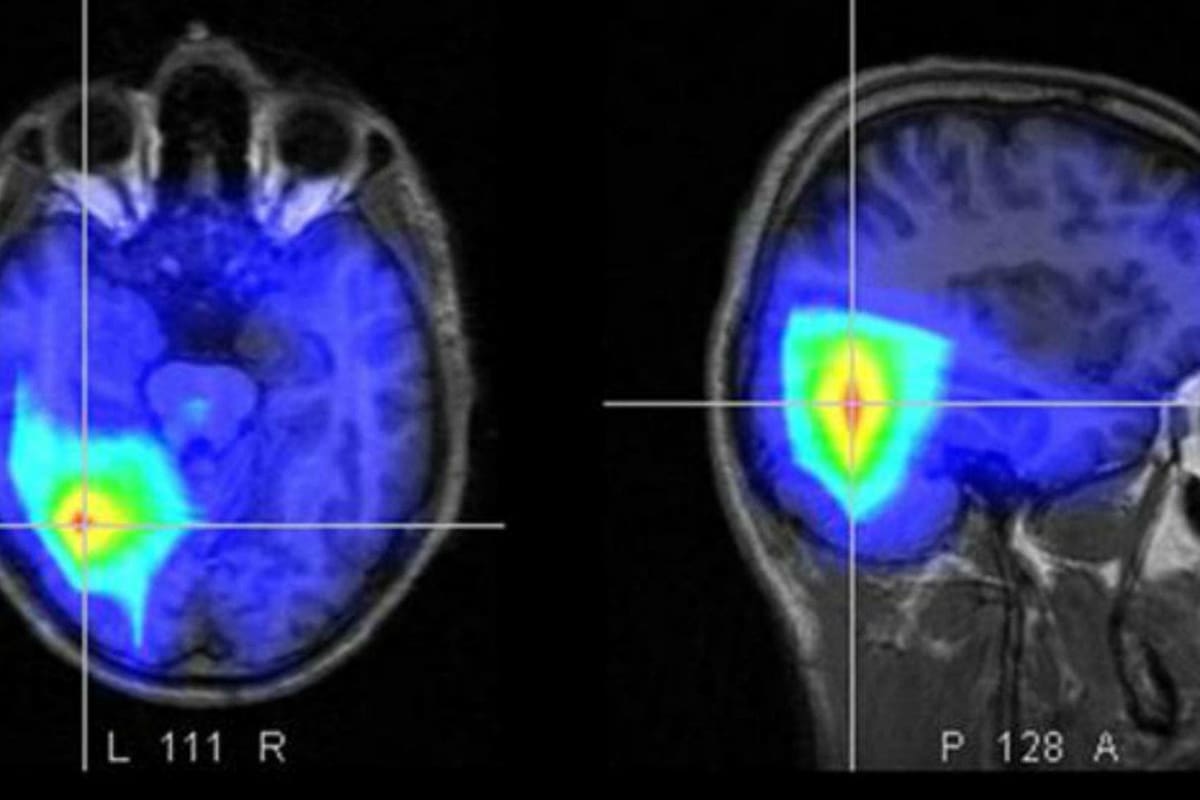

Qué es un ACV

Es una afección causada por la pérdida de flujo sanguíneo cerebral (ACV isquémico) o por el sangrado cerebral (ACV hemorrágico). Datos del Ministerio de Salud de la Nación destacan que el ACV isquémico es el más frecuente y ocurre en el 80% de los casos.